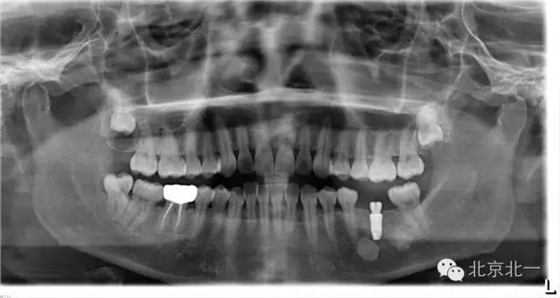

先看一例病例。頜骨內(nèi)單發(fā)高密度影像。是什么?能不能影響種植, 骨島是什么鬼?需要怎么處理?

如已經(jīng)證實(shí)骨島,是可以進(jìn)行種植牙。但是骨島和致密性骨炎不好區(qū)別。 因?yàn)橹旅苄怨茄兹绻M(jìn)行種植必將失敗,切記!切記!切記!

總結(jié):出絕招,如果遇到診斷不明確的骨島或者高密度影像, 最好的方式就是躲避, 不碰及它。

【口腔種植】致密性骨炎/牙骨質(zhì)增生/骨島如何鑒別?

頜骨三種高密度影像的鑒別

3)骨島:

概述:

主要和根尖型骨島鑒別,主要集中位于根尖區(qū)的骨島,

【CBCT表現(xiàn)】:

在CBCT上,根尖型骨島無(wú)低密度帶狀影包繞,與周圍骨質(zhì)分界清晰,具有特征性的毛刷樣邊緣,且其發(fā)生區(qū)域的牙根牙周膜影像連續(xù)、完整、不導(dǎo)致頜骨的膨隆。

右下頜C4根尖區(qū)課件一類圓形高密度影,與周圍骨質(zhì)分界清晰,C4牙周膜影像連續(xù)、完整,下頜骨未見(jiàn)膨隆。